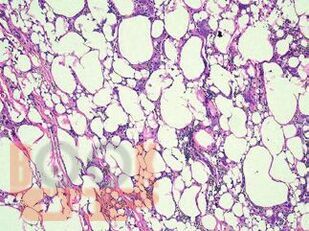

В атласе подробно изложено цитологическое и гистологическое описание всего спектра патологических изменений ткани молочной железы: неопухолевые, пролиферативные процессы, предраковые поражения, доброкачественные и злокачественные опухоли. Кратко представлены данные об этиологии, о патогенезе, молекулярной генетике, клинической картине и лучевых методах исследования различных поражений молочной железы. Подробно описаны дифференциальная диагностика и возможные ошибки морфологической диагностики. Атлас иллюстрирован большим количеством микрофотографий.